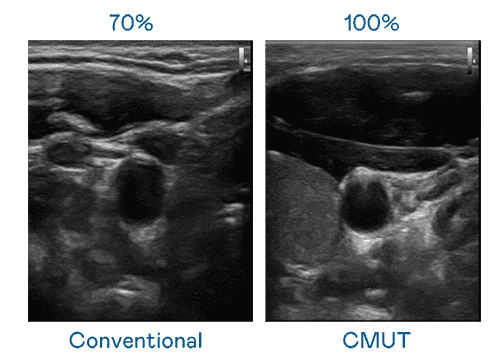

CMUT 技术是一种用电容式微机电元件来产生超音波讯号的技术。。。。与传统 PZT 压电式技术相比,,,CMUT 频宽增加 30%,,更宽频的超音波讯号让影像解析度大幅提升,,,,是实现高影像品质医疗超音波扫描、、促进精准医疗发展的关键技术。。。。

大频宽带来超清晰影像

超音波影像的解析度高低,,,首先取决于探头能发出的讯号频宽。。EBpay CMUT 可提供高清晰的超音波讯号,,提供高频宽、、高灵敏度、、、影像纹理细节更高的超音波影像,,,,协助医护人员缩短影像判读时间及利用精准的医疗影像进行诊断。。。。